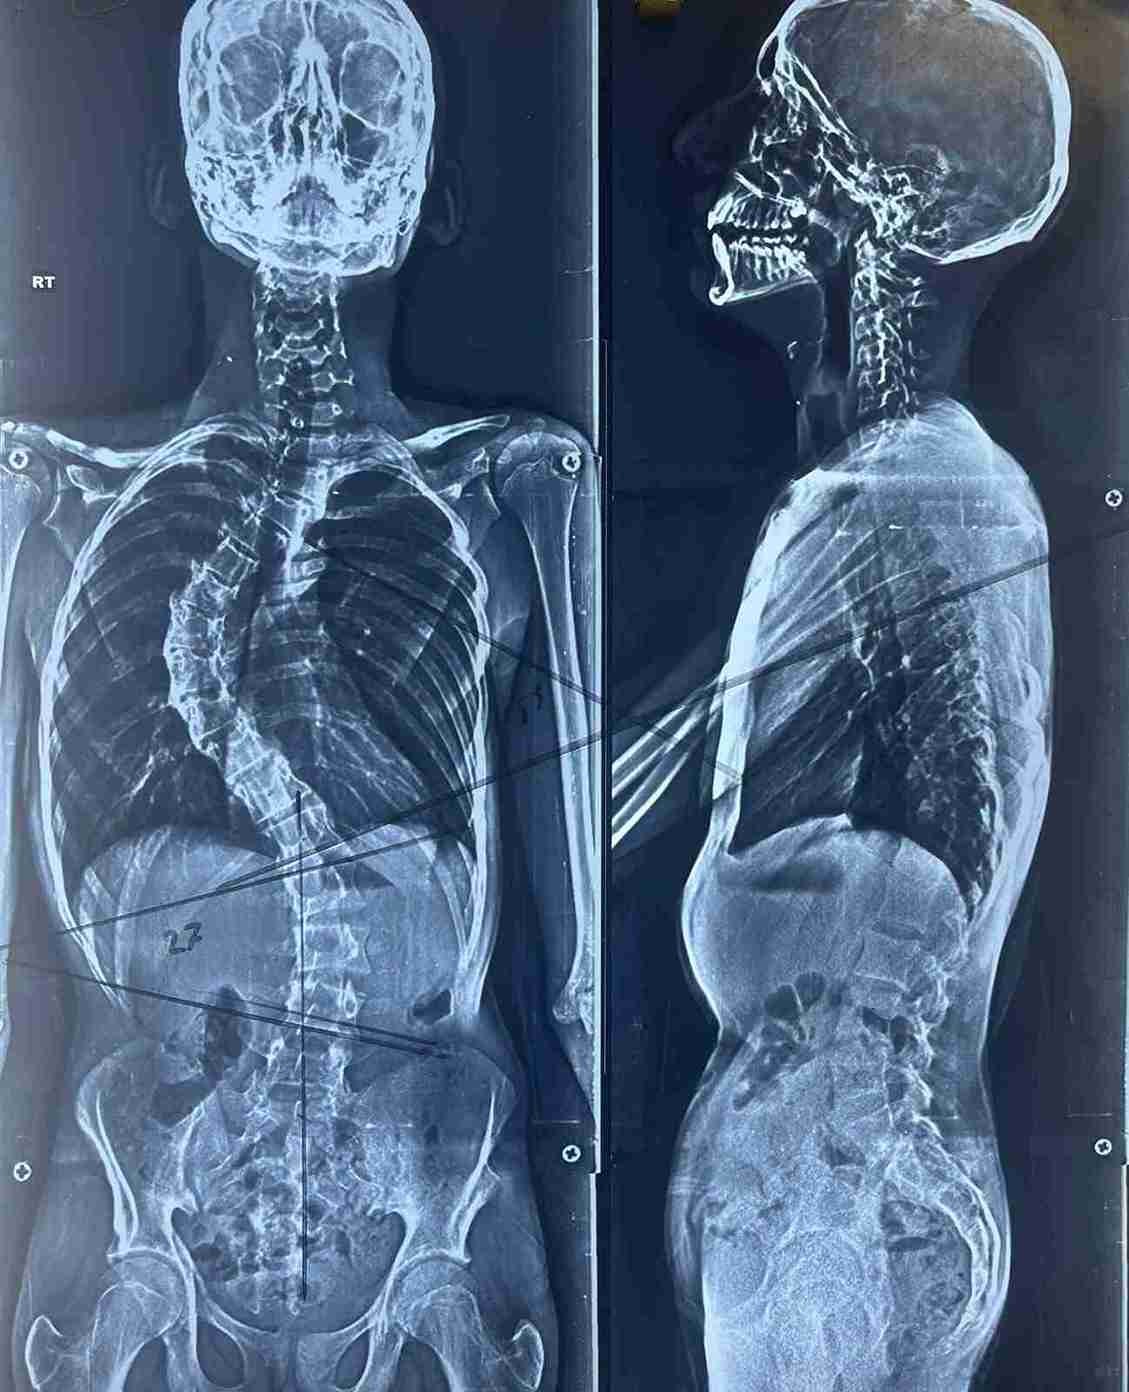

حالة اعوجاج بالفقرات الصدرية

a case of curvature of the thoracic vertebrae

A case of curvature in the thoracic vertebrae of the spinal column was diagnosed and treated. This condition involves an abnormal curvature in the chest area of the spine, which can affect posture, breathing, and cause chronic pain.